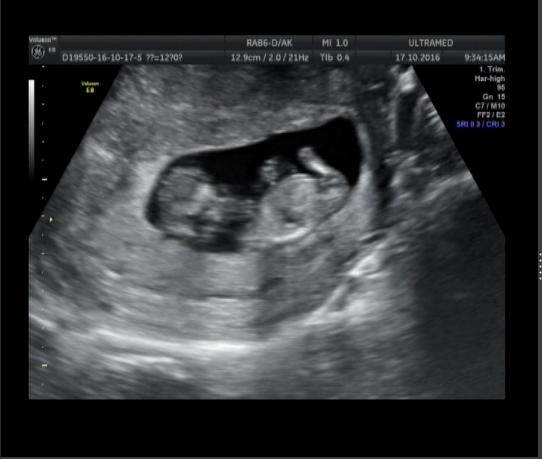

Вопросы про УЗИ, обследования и анализы: что, где, как, когда?А кто у нас? Узи 12 недель ровно. Я пока не понимаю. Тут ножки раздвинуты, посередине видно "колбаску".